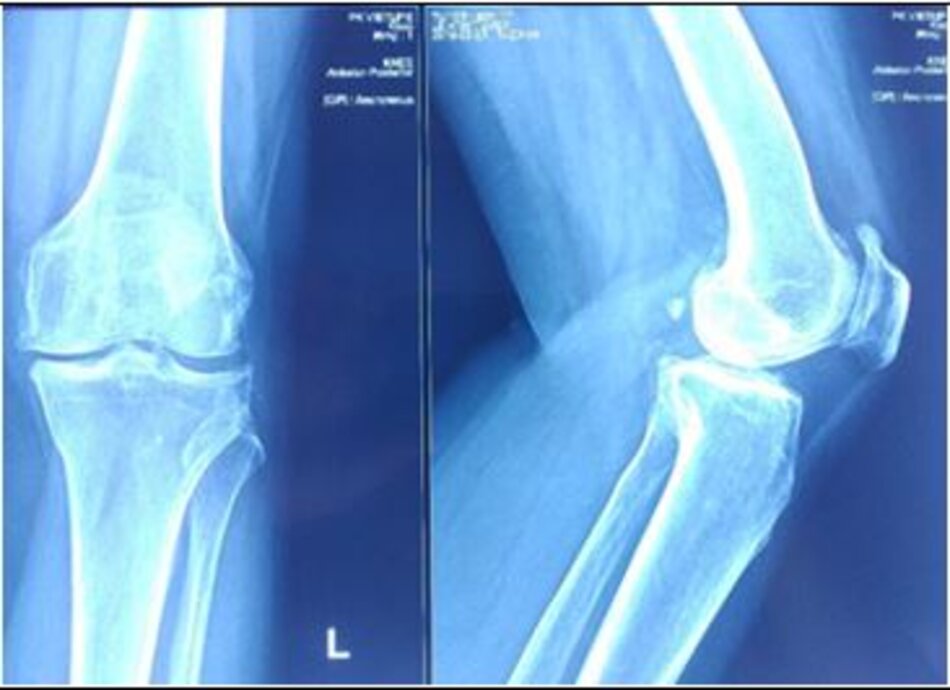

Xquang Khớp gối trái trước mổHình ảnh thoái hóa mâm chày trong

Xquang Khớp gối trái trước mổ. Hình ảnh thoái hóa mâm chày trong

Xquang khớp gối trái sau mổ. Thay khớp gối bán phần có Robot hỗ trợ